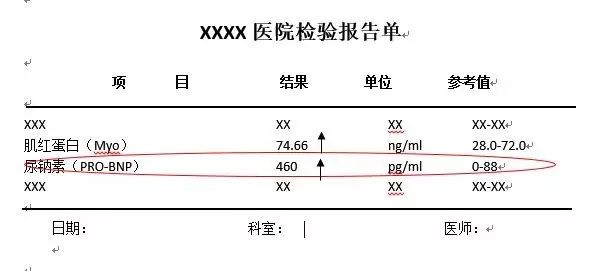

♥BNP(脑钠肽): 用来诊断心衰、评估心衰严重程度和治疗效果的生物标志物。反映的是左右心室、心脏瓣膜的功能。血浆BNP>80ng/L,诊断无症状心衰敏感性高,有利于心衰早期诊断,早期治疗。BNP也可以评估慢性心衰的严重程度和预后,BNP值越高,心衰的预后越差。另外,BNP可以辅助评价心衰治疗效果,降低病死率和住院风险。

如果是怀疑心衰的患者,检查显示BNP≥35pg/ml(或NT-proBNP≥125pg/ml),应及时检查超声心动图,排除心衰的可能。